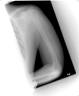

Follow Up

Fracture healing well and fixator removed after three months

Final Results

Patient had full return of elbow motion and clinically excellent result.